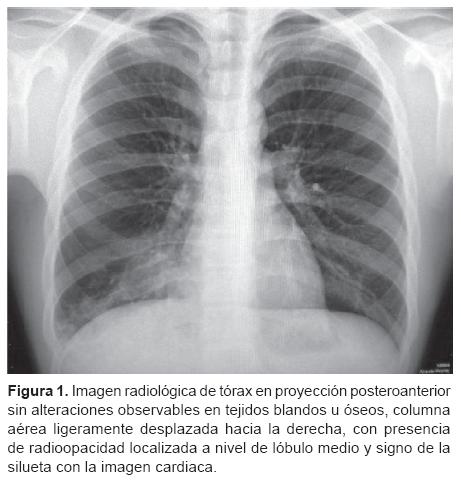

Aspiracion De Cuerpo Extrano Formas De Presentacion Y Complicaciones A Proposito De Cuatro Casos